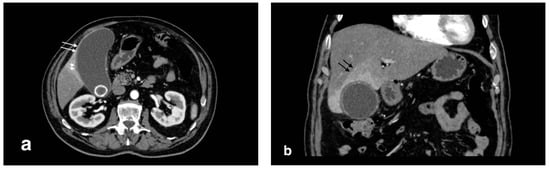

Figure 9.

Liver abscess with pylephlebitis: (a) CT arterial phase; (b) CT portal phase. In the right lobe, V segment, a large hypodense collection with hypoattenuating halo due to intrahepatic abscess (black arrows, (a,b)) with the presence of a hypodensity within the left portal vein lumen due to thrombosis and hyperdensity of portal walls indicative of pylephlebitis better defined in CT portal phase (b) (white arrow).